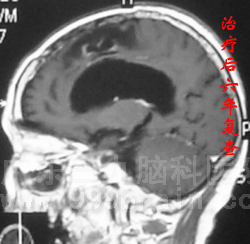

近日,55岁的苏女士回院复查,结果喜人:头颅MR检查未见复发迹象!这已是苏女士术后的第六个年头,复查结果意味着其病情已达到“临床治愈”标准!www.999brain.com

2006年8月,苏女士因突发肢体抽搐2天在当地医院查出左额颞叶占位性病变,大小约4.7×4.5×5.1cm,随即到广东三九脑科医院神经外科求诊。顺利接受手术治疗后,病理检查为少突星形细胞瘤Ⅱ-Ⅲ级,属恶性程度较高的胶质瘤,术后予以放化疗后复查头颅MR显示肿瘤消失。随后几年来她定期复查,未见肿瘤复发征象。2009年12月复查发现原术区出现斑点状异常强化影,为防止肿瘤复发,行2程化疗,治疗后强化影消失。目前距初次治疗已经6年,苏女士状态良好,与常人无异。